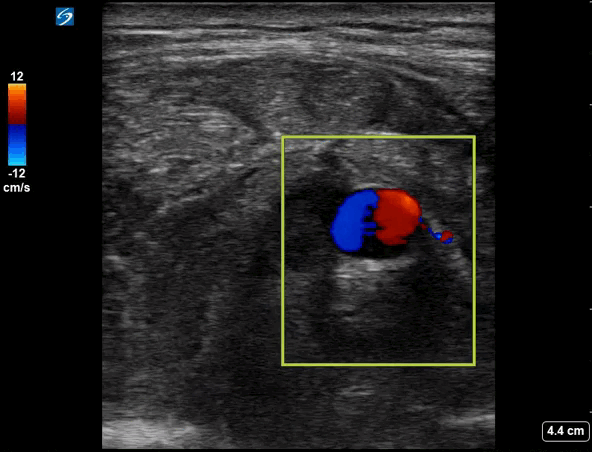

Clip 1 - Right shoulder (Colour doppler)

• This shows a hypoechoic collection below the deltoid muscle with a 7.7mm round pulsating collection.  This demonstrates the ‘ying-yang sign’ on assessment with colour doppler and can be seen to be arising from a vessel – this is the thoracoacromial artery, a branch of the axillary artery.  This is a traumatic pseudoaneurysm and the pseudoaneurysm ‘neck’ can be seen on the right of the image.

Ultrasound has been used to evaluate soft tissue swellings and pseudoaneurysms in post-traumatic injuries and intravenous drug users, and is the imaging modality of choice in psuedoaneurysms[1].  Pseudoaneurysms appear as round pulsating swellings arising from a vessel.  Colour doppler shows the pathognomonic ‘ying-yang’ or ‘pepsi’ sign which is due to turbulent flow of blood within the pseudoaneurysm.  Remember the mnemonic ‘BART’ for direction of flow with colour doppler – Blue Away, Red Towards. Blue indicates flow away from the US probe, Red indicating flow towards the US probe.